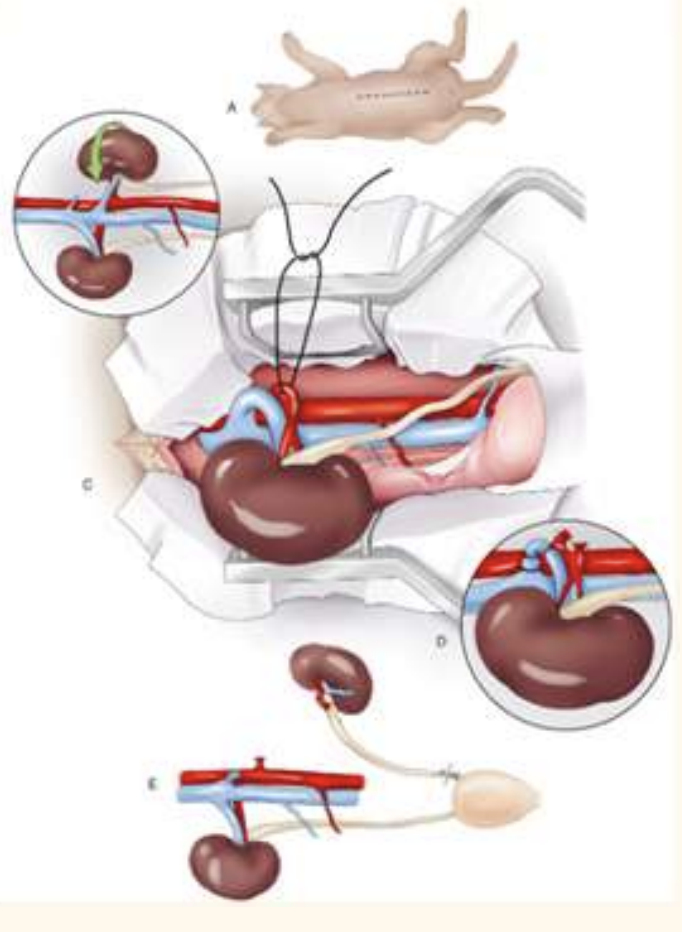

Uretero-nephrectomy

ventrla midline approach

identify kidney with duodenal/ colonic nerves

kidney sit in fatty pounch (retoperitoneal flat)—> blunt dissect kidney w digit

identify arterys and veins. —> thicker is artery, ;

circumfrential/ transfixing suture to ligate ligate a first (prevent engorgement)

remember to place ligature on each side and resect in between

elevate kidney, dry swap all the way down ureter down bladder

suture x2, resection as close to bladder as possible